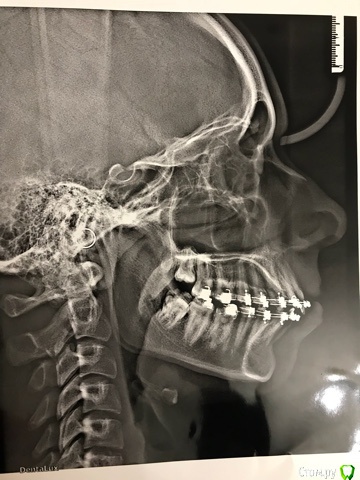

Брекеты носим два года, прочитав информацию в интернете, понимаю, что у нас прямо взаимоисключающие показатели, предложенное лечение - компромисс. При дефиците места на нижней челюсти лечение без удаления чревато осложнениями.

Через два месяца планируется снятие брекетов. На выходе имеем: профиль лица выпуклый, некрасивый, но по сравнению с тем, что было улучшен. Сагитальная щель 3мм. На нижней челюсти оголились корни передних резцов. Были на консультации у хирургов, назначили день операции по уздечке нижней губы, которая даёт натяжение, но в день операции проводить не стали, сказали - лучше после снятия брекетов, чтобы не травмировать десну перед снятием. Озвучили про подвижность нижних зубов и выход корней из костной ткани. Рекомендовано удаление 8-к.

По поводу верхних резцов, до установки брекетов режущие края зубов были на одном уровне, видимо, ошибка в позиционировании брекетов, ТК в ходе лечения один верхний резец поднялся выше и отклонялся от вертикали, выровнять края не удалось, но ТК, как пишут, пациентов в первую очередь волнует косметика, дочка переживает, что очень бросается в глаза. Прочитала в интернете в блоге одного ортодонта, что такая ошибка исправляется либо изгибом дуги либо Переустановкой новых брекетов, поэтому он работает с брекетами средней ценовой категории и переустанавливает в случае отклонения. На этой неделе плановый прием у ортодонта, хочу предложить : переустановить на два верхних резца новые брекеты, а на нижней челюсти - принесу новый трг (прикреплен в предыдущем сообщении) и как-то надо решать проблему с выходом корней из кости, если такая действительно есть, ТК хирурги в направлении к ортодонту не написали такое, а только озвучили, а написали на консультацию по поводу удаления 8-к.

Добрый день, так никто и не ответил. Прочитала информацию в интернете, самостоятельно с помощью линейки и транспортира измерила углы SNA и SNB, точки определила на снимке ТРГ по описанию опять же в интернете. По измерениям получился угол SNA 85 градусов, угол SNB 80. Результат понимаю так, на грани нормы, но норма, нет скелетных отклонений для вывода о переднем положении верхней челюсти и заднем положении - нижний. Вывод патология - в зубоальвеолярных отростках. Чтобы бы быть спокойной в правильности лечения ребенка, приходится изучать информацию и пытаться ее переварить на дилетантские уровне.